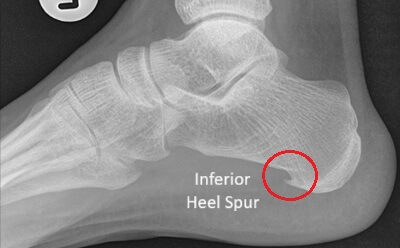

Foot bone spurs are areas of extra bone growth and are the most common cause of a hard lump on bottom of foot, usually on the heel or metatarsals.

Symptoms: Hard lump bottom of foot, sharp, stabbing pain when standing or walking.

Causes: Repetitive stress, tight shoes, injuries, arthritis or biomechanical changes.

Treatment: Exercises, orthotics, medication, and sometimes surgery.

See the Bone Spurs article for full treatment details.